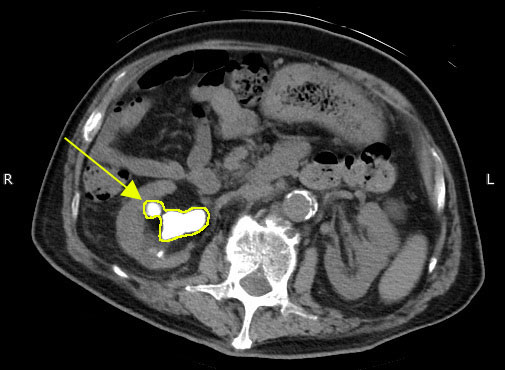

腎結石のCT

※腎結石のCT画像